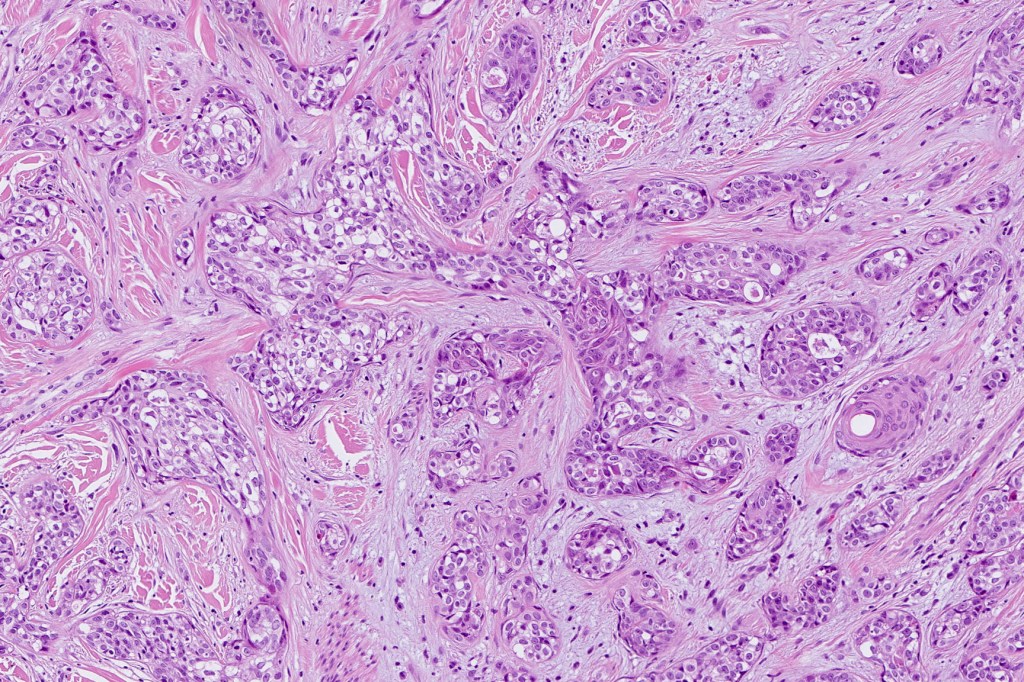

•Widely infiltrating biphasic tumor

•Superficial SCC

•Adenocarcinoma in deeper reaches

•Variable pleomorphism and mitotic activity

•Deep part may show both ducts and glands